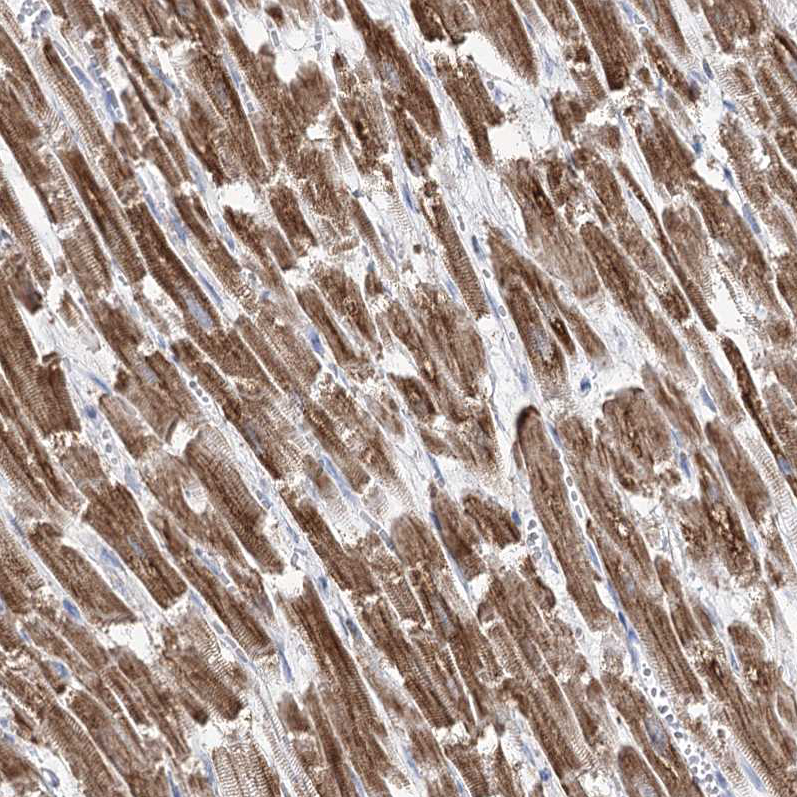

Immunohistochemistry analysis in human heart muscle and pancreas tissues using HPA036745 antibody. Corresponding PDHB RNA-seq data are presented for the same tissues.